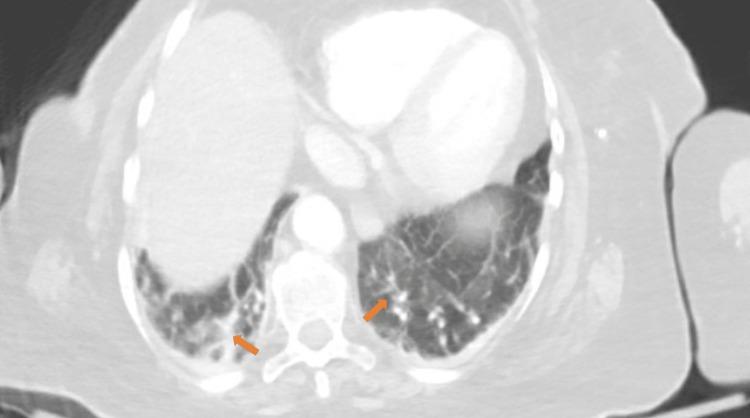

()and coronavirus disease 2019 (COVID-19) infections can have overlapping symptoms. Recently, the association and outcomes of coinfection have been studied. We present the case of an 83-year-old lady with Parkinson's disease (PD) who was admitted with pneumonia secondary to severe acute respiratory syndrome coronavirus-2 (SARS-CoV-2) infection. She was treated with empiric antibiotics ampicillin-sulbactam and azithromycin, along with antiviral therapy remdesivir and baricitinib, and dexamethasone. The patient developed severe infection with a leukemoid reaction. She was treated with intravenous metronidazole and oral vancomycin without any improvement. Before she could receive a fecal microbiota transplant, her infection progressed to fulminant colitis, and she required emergent surgery. The patient developed several complications post-surgery and succumbed to the severe illness. Our patient's multiple comorbidities and an underlying COVID-19 infection predisposed her to severe illness. This case emphasizes the long-standing discussion on antibiotic stewardship and encourages a debate on the role of immunosuppressant antiviral medications and underlying PD in predisposing patients to a severe infection.

()与2019冠状病毒病(COVID-19)感染可能有重叠症状。最近,已对合并感染的关联和结果进行了研究。我们报告一例83岁帕金森病(PD)女性患者,因严重急性呼吸综合征冠状病毒2(SARS-CoV-2)感染继发肺炎入院。她接受了经验性抗生素氨苄西林-舒巴坦和阿奇霉素治疗,同时接受了抗病毒治疗瑞德西韦和巴瑞替尼以及地塞米松治疗。患者发生了严重感染并伴有类白血病反应。她接受了静脉注射甲硝唑和口服万古霉素治疗,但无任何改善。在她能够接受粪便微生物群移植之前,感染进展为暴发性结肠炎,她需要紧急手术。患者术后出现了多种并发症,最终死于重症。我们患者的多种合并症和潜在的COVID-19感染使她易患重症。该病例强调了关于抗生素管理的长期讨论,并鼓励就免疫抑制性抗病毒药物和潜在的帕金森病在使患者易患严重感染方面的作用展开辩论。